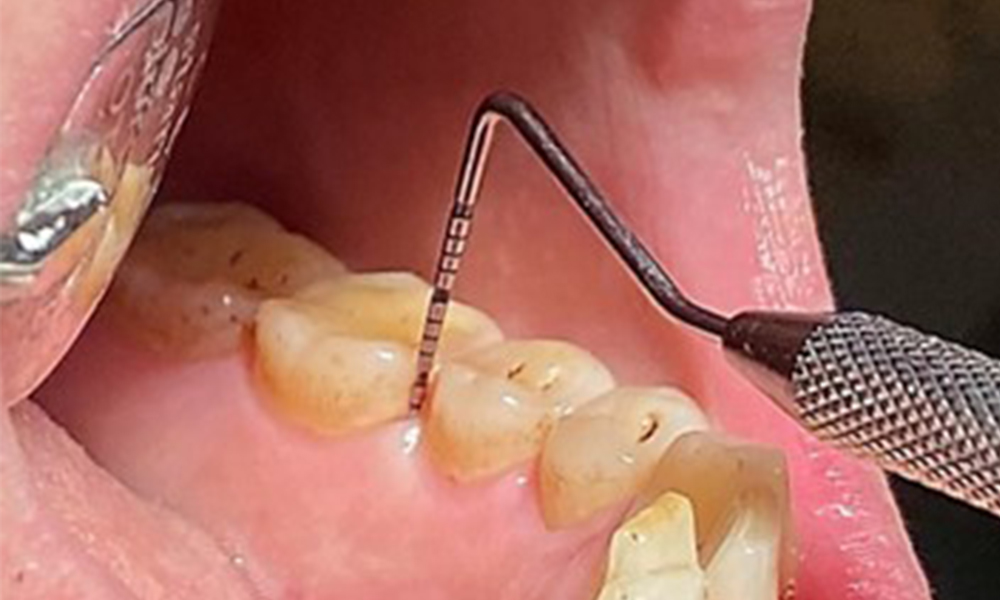

En raison d'un état de santé général par ailleurs favorable, les besoins déterminés lors de l'examen intra-oral seront déterminants pour le traitement. Il sera essentiel de déterminer périodiquement les profondeurs de sondage. Le saignement gingival diminue chez les fumeurs, c'est pourquoi le diagnostic clinique de la parodontite ne peut se faire que par sondage (Fig. 7). En se concentrant exclusivement sur la détermination des indices de saignement, on risque d'occulter une parodontite ou une gingivite existante. (5)

Sondage en poche (BOP) avec représentation de la dent 36 linguale

Fig. 7 Sondage en poche (BOP) avec représentation de la dent 36 linguale, © Dr R. Krapf